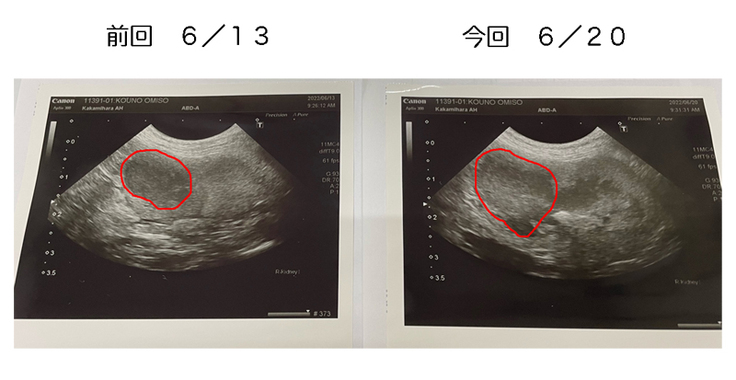

しかしながら、前回に投与が出来なかった事もあり、今回のエコー画像では、腫瘍が大きくなってしまいました。

やはりかなり強固な腫瘍らしく、おみその体調を考慮しながら治療はおこなって行きますが、完全寛解には至らないかもしれないとの事でした。今後の状況では、寛解を目指すのではなく現状を保つ治療も考えて行く必要が出てくるかもと・・・。

毎週、抗がん剤の投与が出来れば、腫瘍も大きくはなってこないと思うので、おみその体調を気遣い、毎週治療出来るように頑張ります。